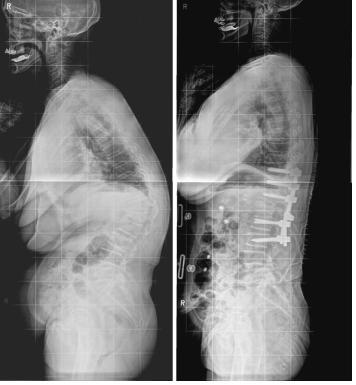

| △ 척추후만증 수술전(왼쪽)과 새 절골술로 수술한 후의 엑스레이 사진. <강동경희대병원 제공> |

강동경희대병원 척추센터 신경외과 조대진 교수팀은 골다공증을 동반한 '외상성 척추후만증'(등굽음)으로 6개월 이상 치료를 받았지만 효과가 없었던 환자 13명에게 자체 고안한 새로운 절골술을 시행한 결과 굽었던 등이 30~40도 가까이 펴지면서도 기존 치료법보다 합병증은 적은 것으로 나타났다고 13일 밝혔다.

그러나 이번에 개발한 절골술은 허리 뒷부분만 절개한 뒤 뼈의 일부분만 절제하고 이어붙이는 방식으로, 수술 시 출혈량을 줄이는 것은 물론 동시에 추간판(디스크)까지 제거함으로써 교정각도를 높일 수 있다고 의료진은 설명했다.

조대진 교수는 "환자가 다치기 이전 상태의 곧은 척추를 만들기 위해 다양한 뼈절제 수술과 전후방 교정술이 사용되고 있지만 허리 뒷부분만 절개하는 골절술로 수술시간을 줄이고, 수술 시 출혈량과 합병증을 줄일 수 있다는 보고는 이번이 처음"이라고 말했다.